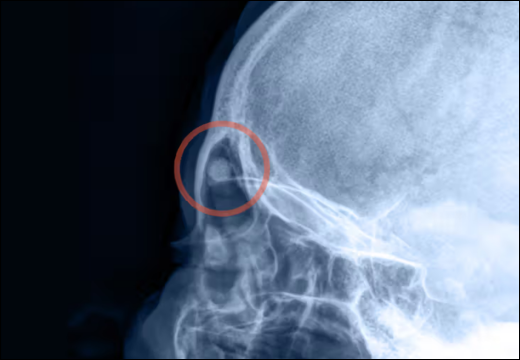

- X-Ray

- Temporal/Mastoid Osteomas: Lesions in or around the ear region can lead to cosmetic deformity, hearing difficulties, or local discomfort.